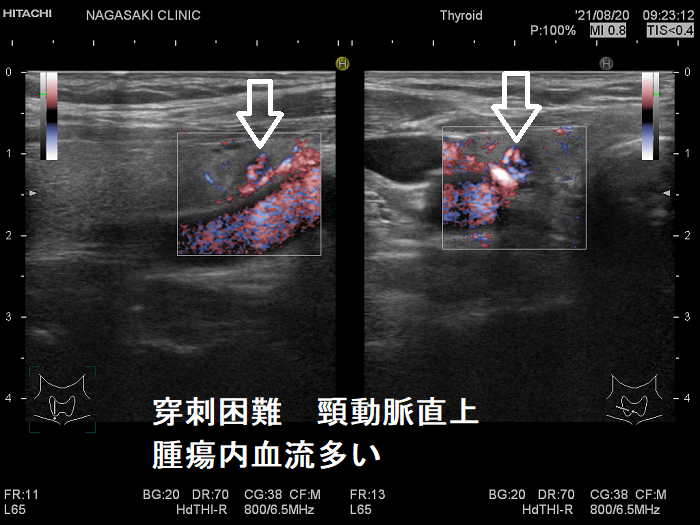

甲状腺穿刺細胞診の主な有害事象の一つは穿刺時出血、穿刺後出血;最悪、気道閉塞により窒息。注意しても唾を飲む方におこる。用手圧迫、再度、超音波エコー、造影CT、喉頭ファイバー行い出血・喉頭腫大を確認後入院。甲状腺機能亢進症/バセドウ病、TSH高値の重度甲状腺機能低下症は甲状腺内部血流が異常増加し穿刺で大出血の危険。甲状腺ホルモン正常化し血流低下を待つ。頚動脈に接する・連鎖して拍動する、下甲状腺動脈直下の小さな甲状腺腫瘍は穿刺難。甲状腺血管腫は何度穿刺細胞診しても血液成分のみで穿刺後出血の危険。最下甲状腺動脈穿刺で大出血。

穿刺細胞診するには、あまりにリスクが大きく、断念せざる得ない場合があります。たとえば、

- 頚動脈に接する小さな甲状腺腫瘍

- 頚動脈近傍で、頸動脈に連鎖して拍動する小さな甲状腺腫瘍

甲状腺乳頭癌の可能性があるため、穿刺細胞診したくても、頚動脈や気管を刺してしまう危険を考えれば断念するのが正しいと思います。「退く勇気」も大切なのです。その代わり、甲状腺腫瘍が大きくならないか、腫瘍マーカーは上昇しないか、定期的に経過を見る必要があります。